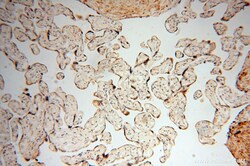

16900-1-AP IHC

Full details

Method: Other validation